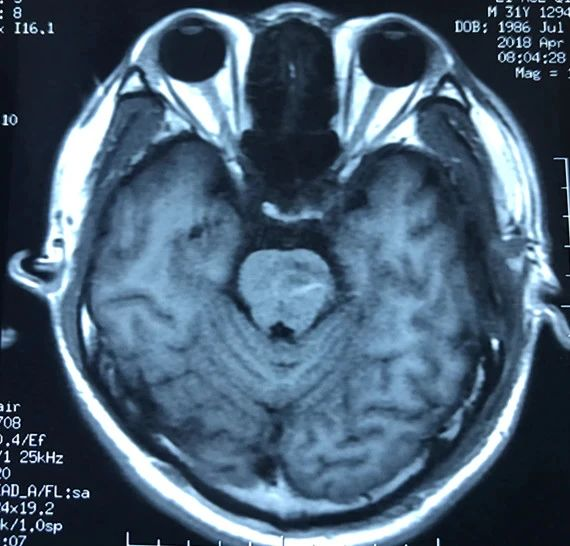

术后磁共振显示脑干病变消失